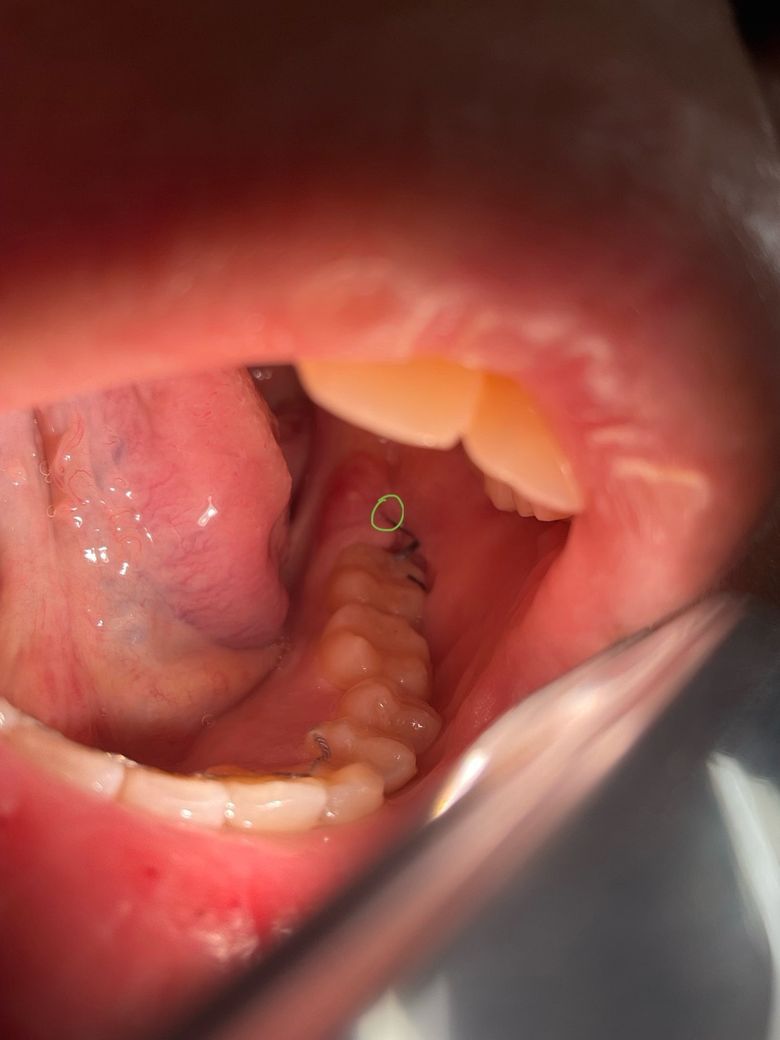

(사진O) 사랑니 발치 후 실밥 관련 질문입니다

사랑니 발치 후 실밥 묶음 두개 묶어 주셨는데요

실밥 한 묶음은 별 이상이 없는데요

초록색 동그라미 부위에 두번째 묶음의 실밥이 있습니다

실밥 매듭이 두 갈래로 나뉘어져 있는데요 한 갈래는 정상인데 나머지 한 갈래는 발치 후 생성되는 육아조직? 안쪽으로 들어간듯 합니다

다음주 월요일 11일에 실밥 제거 하러 가는데 그 전에 잇몸이 아물어서 안 보이게 된다던지 문제 생기거나 하진 않겠죠??

• 1번 째 사진